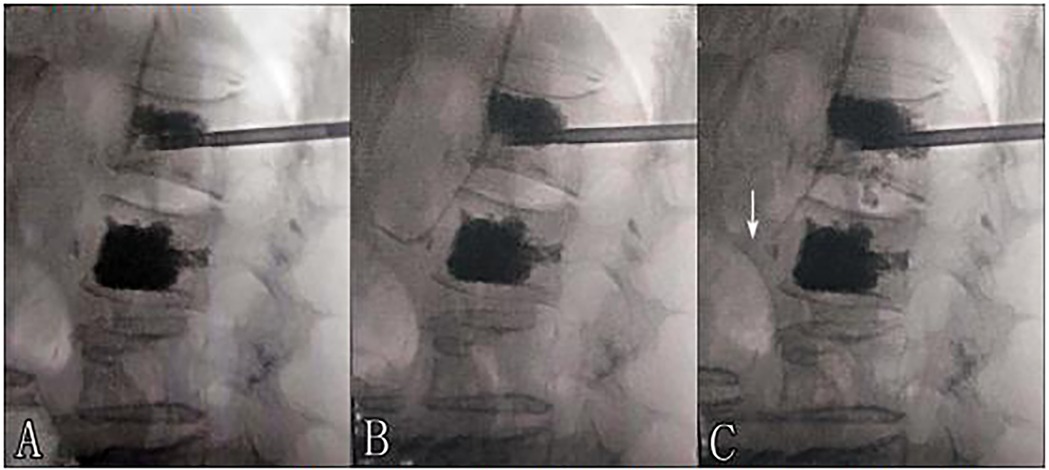

A 69-year-old woman was admitted to our hospital due to refractory back pain for approximately one month. Preoperative evaluation revealed that the patient had a bone mineral density T-score of −3.2 at L1-L4, indicating severe osteoporosis, imaging findings from MRI showing fresh osteoporotic vertebral compression fractures at L1 and L2 (characterized by T1-weighted hypointensity and T2-weighted hyperintensity with edema), while lower extremity Doppler ultrasound detected no pre-existing venous thrombosis. The routine preoperative medical evaluation was normal. Given her symptoms and spine images, she was treated with percutaneous vertebroplasty under local anesthesia (1% lidocaine) with continuous monitoring of heart rate, blood pressure, and oxygen saturation. Bone cement was typically infused into the vertebral body using a unilateral transpedicular approach, with intermittent anteroposterior and lateral fluoroscopy guidance. The percutaneous vertebroplasty procedure for L2 was completed successfully and approximately 4.5 ml of bone cement was infused (polymethylmethacrylate, viscosity: high, mixed for 3 min before injection). Then, the percutaneous vertebroplasty procedure for L1 was performed as follows. When the injection volume reached approximately 1.5 ml, anterior cement leakage in the paravertebral venous system was detected on lateral fluoroscopy. Immediately, vital signs were observed to be continuing smoothly with no obvious fluctuations (HR 72 bpm, BP 135/85 mmHg, SpO2 99%). Additionally, there were no complaints of cardiorespiratory discomfort by the patient. As the vertebral fill was inadequate, we continued the bone cement injection procedure. However, the trajectory tracking of cement leakage in the paravertebral venous system was gradually prolonged with continuous additional cement injection (Figure 1). When the cement injection dose reached approximately 4 ml, cement disk space extravasation was detected and we terminated the procedure at that time. The postoperative outcome was seemingly good and had no symptoms such as dyspnoea, coughing, haemoptysis, dizziness or palpitation. However, the postoperative thoracolumbar x-ray presented that multiple tubular and branching cement emboli were scattered throughout the lungs (Figure 2). Intraoperative lateral fluoroscopy data were analysed retrospectively, and we detected that sustained cement injection resulted in the migration of the distal part of the prolonged cement leakage tracks in the paravertebral venous system on the last lateral fluoroscopy. The subsequent treatment consisted of two days of conventional postoperative treatment and electrocardiogram monitoring, with no use of anticoagulation. The patient's vital signs continued smoothly until discharge. The patient was satisfied with the operation because her back pain was significantly relieved. With a one-year clinical follow-up after discharge, she remained asymptomatic. During the follow-up after discharge, it was noted that the patient developed pneumonia more than one year after leaving the hospital. Computed tomography (CT) at the local hospital confirmed the presence of bone cement emboli within the pulmonary artery branches, as illustrated in Figure 3, following successful treatment, the patient recovered uneventfully and was discharged from the hospital.

Figure 3. Panels (G,H) show chest computed tomography (CT) scans acquired more than one year postoperatively, which demostrated bone cement emboli within the pulmonary artery branches.